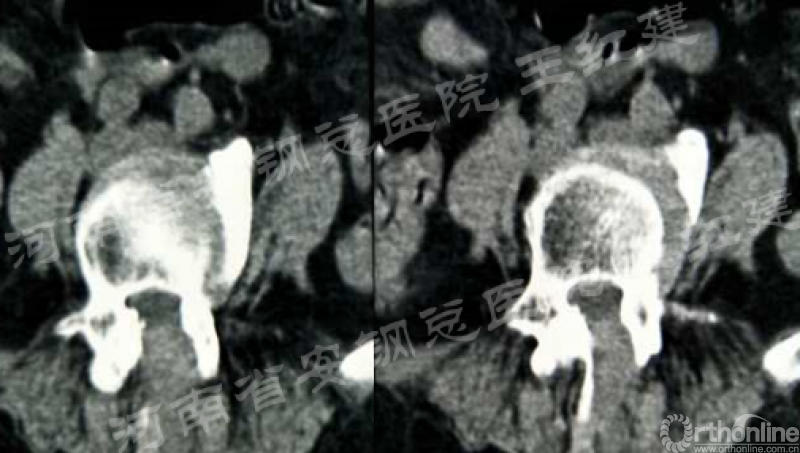

四、经皮螺钉技术固定

在固定的步骤可以先期进行经皮螺钉置入,再进行融合器的置入,进而实现充分固定。

椎弓根植入加压固定

单边椎弓根植入加压固定

双侧椎弓根植入加压固定

手术步骤:先期经皮螺钉置入、再进行融合器的置入